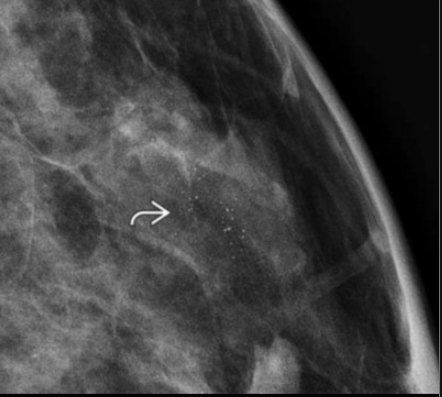

best classification of calcs?

Punctate

usually benign, but watch how they change over time, may diffx BIRADS 3 (watch and wait) from BIRADS 4 (Bx)